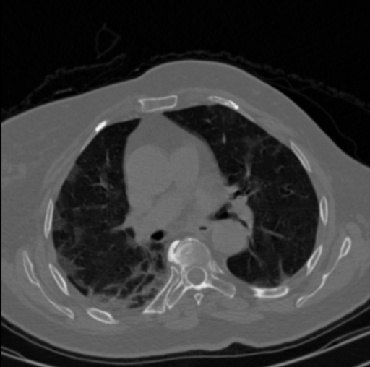

Early and reliable COVID-19 diagnosis based on chest 3-D CT scans can assist medical specialists in vital circumstances. Deep learning methodologies constitute a main approach for chest CT scan analysis and disease prediction. However, large annotated databases are necessary for developing deep learning models that are able to provide COVID-19 diagnosis across various medical environments in different countries. Due to privacy issues, publicly available COVID-19 CT datasets are highly difficult to obtain, which hinders the research and development of AI-enabled diagnosis methods of COVID-19 based on CT scans. In this paper we present the COV19-CT-DB database which is annotated for COVID-19, consisting of about 5,000 3-D CT scans, We have split the database in training, validation and test datasets. The former two datasets can be used for training and validation of machine learning models, while the latter will be used for evaluation of the developed models. We also present a deep learning approach, based on a CNN-RNN network and report its performance on the COVID19-CT-DB database.